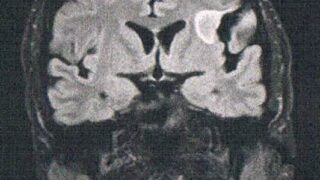

GLIOMA:手術後120ヶ月目の検査

手術から10年が経過した。半年ごとの定期検査です。検査概要びまん性星細胞腫グレード2(悪性転化しやすい腫瘍)MRI検査: 造影剤なし / 造影剤あり造影剤ありの場合:4時間前から絶食し、MRIの1時間前に血液検査を済ませる。診断結果初めて前...